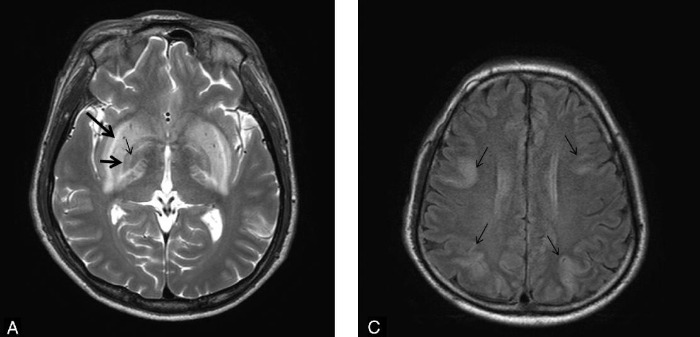

Визуализация мозга чаще всего выявляет его атрофию и увеличение желудочков. Тем не менее иногда, в ограниченном числе случаев при МРТ головного мозга можно обнаружить специфические изменения в области базальных ганглиев, хотя подобные признаки могут сопровождать и метаболический ацидоз, и метаноловую интоксикацию. Изменения, лучше всего заметные в режимах Т2-WI/FLAIR, представляют собой гиперинтенсивные четко очерченные границы скорлупы (латерально — наружная капсула, медиально — внутренняя капсула, внутренняя и наружная мозговые пластинки) с обеих сторон и в целом по форме несколько напоминающие вилку. По сути это является отображением диффузного вазогенного отека базальных ганглиев из-за нарушения процессов ауторегуляции.

- Kim D. M., Lee I. H., Song C. J. Uremic encephalopathy: MR imaging findings and clinical correlation //American Journal of Neuroradiology. – 2016.